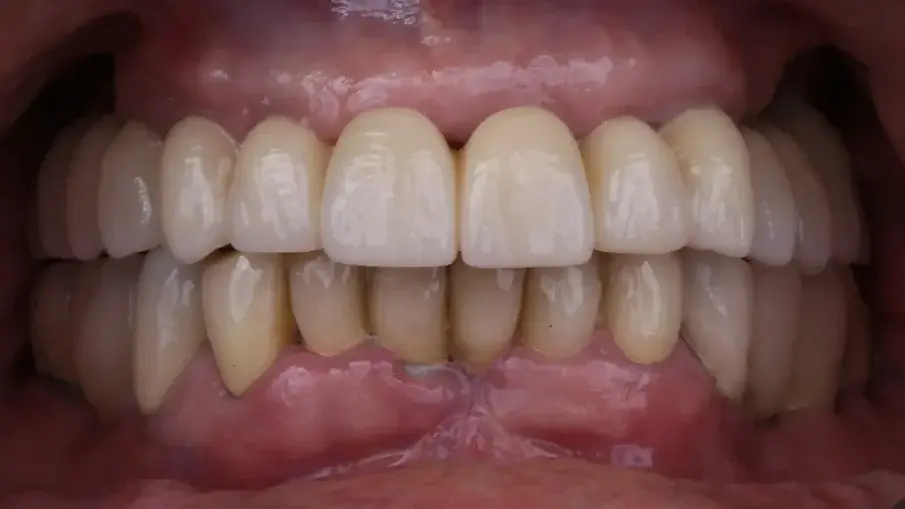

При последната среща беше поставена окончателната хибридна винтово-фиксирана протеза. Окончателната протеза се състоеше от CAD/CAM титанова рамка, завинтена към всички импланти, и три монолитни циркониеви протезни сегмента, залепени отгоре (фиг. 18а–в). Беше оценена оклузията и пациентът беше включен в четиримесечна програма за поддържане. При последната контролна визита (една година след поставянето на имплантите) всички импланти бяха успешни и пациентът беше удовлетворен от новата протеза (фиг. 19–22).

Фиг. 19: Окончателна протеза при едногодишното проследяване, фронтален изглед.